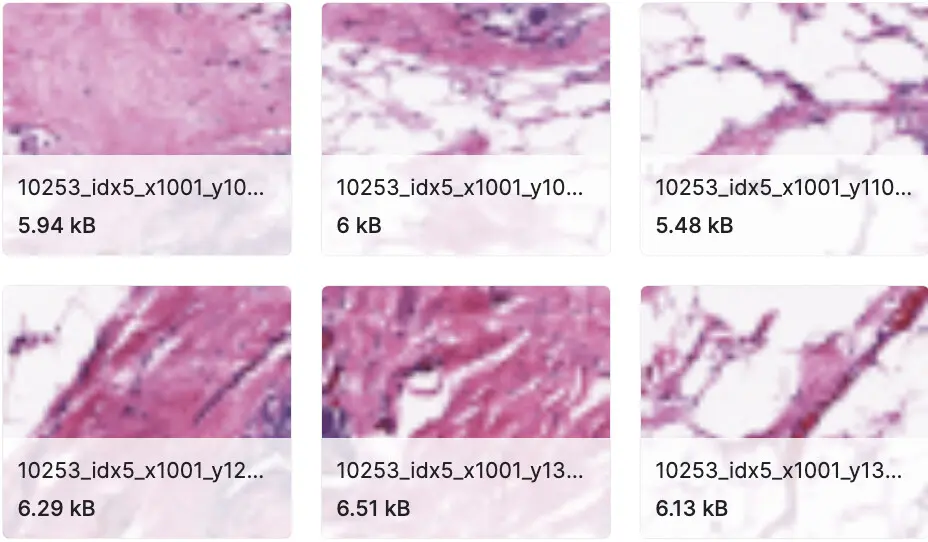

乳房组织病理学图像

原始数据集包含以 40 倍扫描的 162 个完整的乳腺癌 (BCa) 标本幻灯片图像。从中提取了 277,524 个大小为 50 x 50 的补丁(198,738 个 IDC 负值和 78,786 个 IDC 正值)。每个补丁的文件名格式为:u_xX_yY_classC.png — > example 10253_idx5_x1351_y1101_class0.png。其中 u 是患者 ID (10253_idx5),X 是裁剪此补丁的 x 坐标,Y 是裁剪此补丁的 y 坐标,C 表示类,其中 0 是非 IDC 和1 是数据中心。